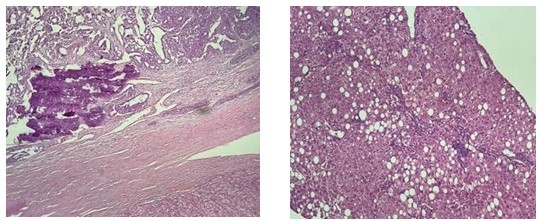

La patología definitiva encontró tumor maligno multinodular con extensas áreas de necrosis de patrón histológico heterogéneo, con áreas sólidas de aspecto epiteloide con células de abundante citoplasma y núcleos vesiculosos con nucléolo prominente, otras áreas con un patrón mixto con células de aspecto inmaduro (Figura 7 y 8). Inmunohistoquímica (Cuadro 1).

Teniendo como hallazgos morfológicos e inmunohistoquímicos compatibles con carcinoma mixto de componente hepatocarcinoma (30 %) y hepatoblastoma (70 %).